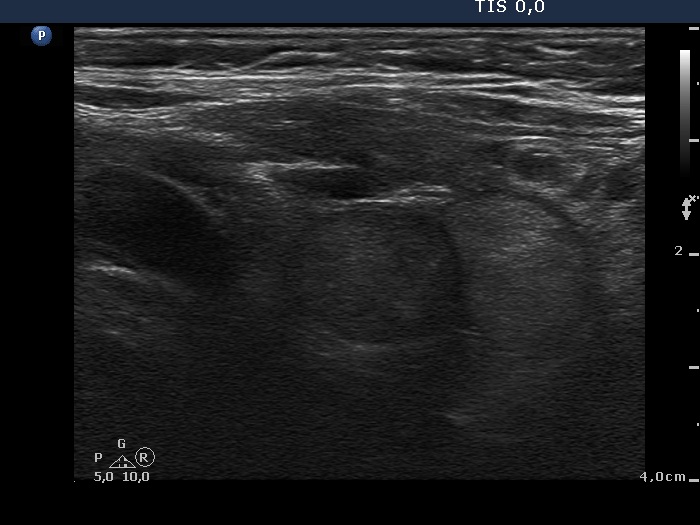

Discrete lesion or nodule in Hashimoto's thyroiditis - case 4 (104) (ultrasonographic picture 6)

Left lobe, another longitudinal view. The doubtful hypoechogenic lesion and an echonormal pseudonodule are presented.